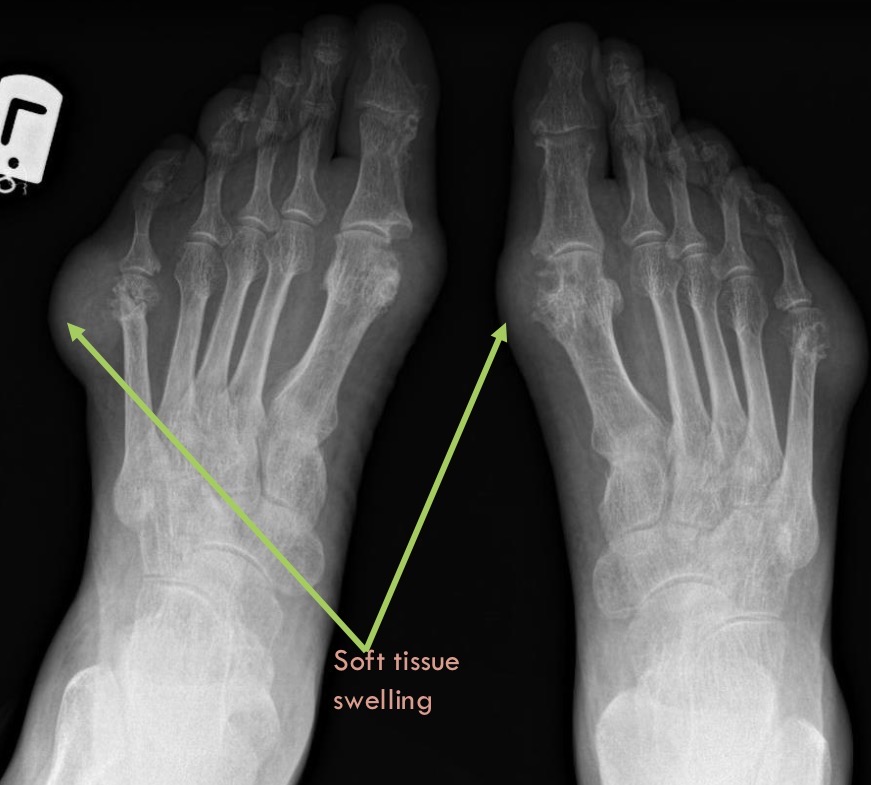

Gout ⭐

Soft tissue swelling

Well defined, punched-out erosions (rat bite)